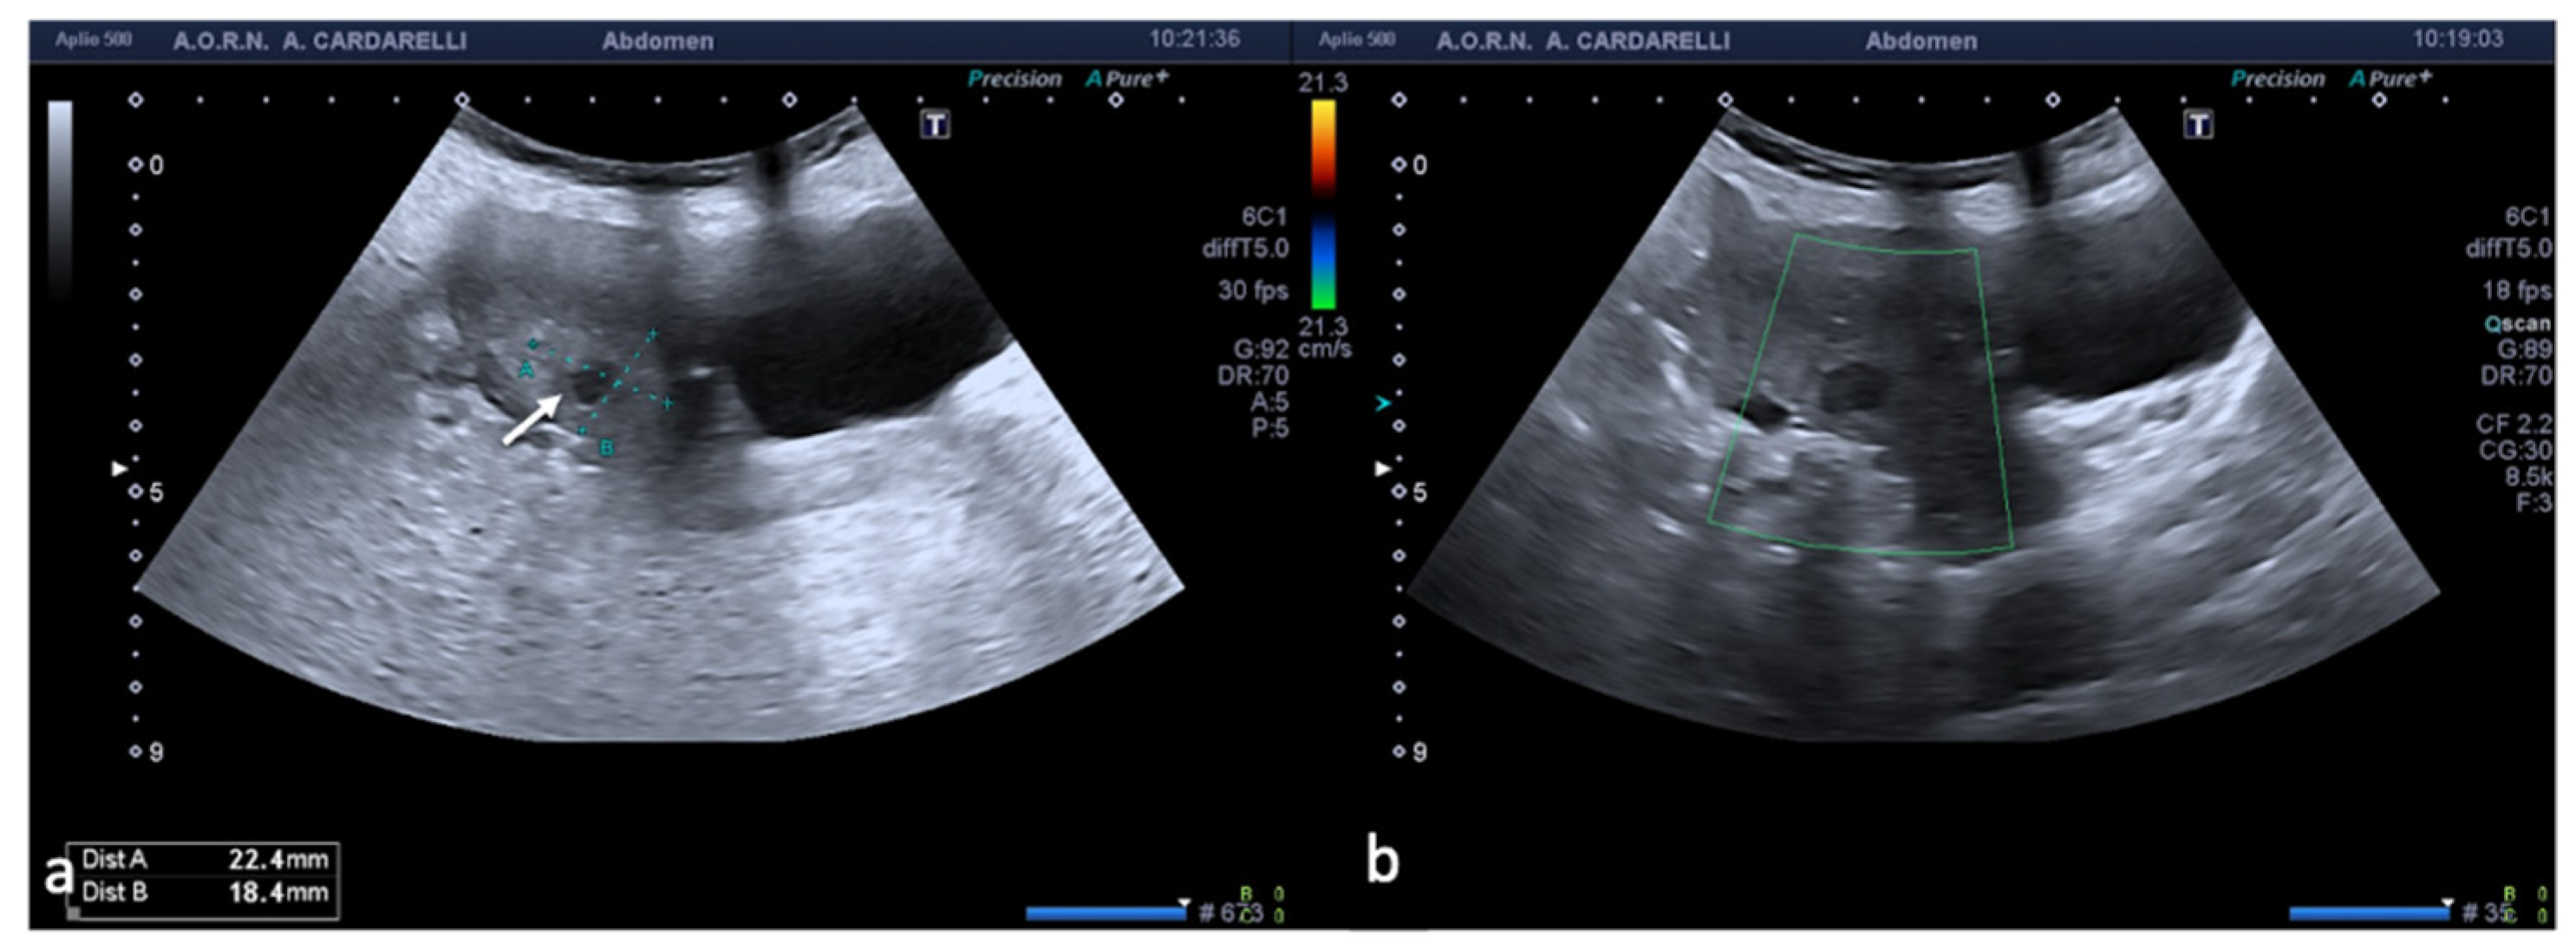

Since it is defined as a surgical emergency, an early differential diagnosis including other genitourinary and gastrointestinal conditions is essential to preserve the ovaries. The clinical symptoms are characterized by acute and sudden pain, sometimes associated with nausea and vomiting with the finding of a palpable pelvic mass and signs of peritonitis [1,3]. The initial assessment of a suspected adnexal torsion requires an US examination, which allows an increase in the volume of the ovary to be observed, which is generally greater than 4 cm, with or without an associated mass (Figure 1).

The twisted and congested peduncle may appear as an indistinct adnexal mass adjacent to the twisted ovary. The colour Doppler examination allows for the assessment of the degree of torsion, the time elapsed from the beginning of the disease and therefore the degree of vascular compromise [1,2,3,4,5]. Vascular colour Doppler signals in the gonadal tissue are generally absent and this allows for a confident diagnosis with a positive predictive value of 94% (Figure 1).

Figure 1. Adnexal torsion of giant mature cystic right teratoma. Axial TSA-US image (a) shows a mostly echogenic mass (caliper) with some sound attenuation. On power Doppler (b) no adnexal vascularization is detected.